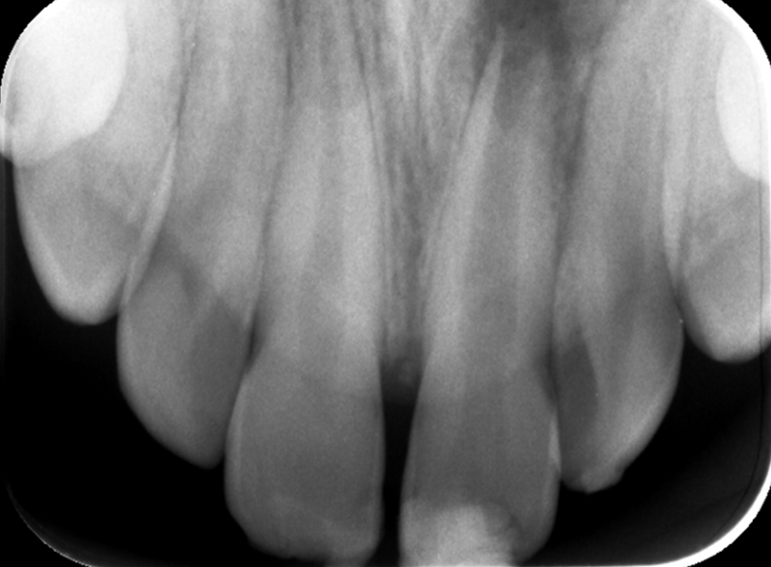

Root canal treatment including apexification of an immature incisor following dental trauma.